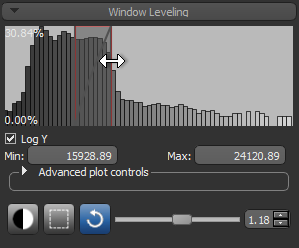

- Adjust window leveling, as required (see Window Leveling).

- Select the Define range option in the Range box on the ROI Tools panel.

- Drag the left or right Range sliders to change the minimum or maximum values of the intensity range or enter the required values in the Min and Max edit boxes.

- Verify the selected range on other images in the image stack and other views of the dataset, recommended.